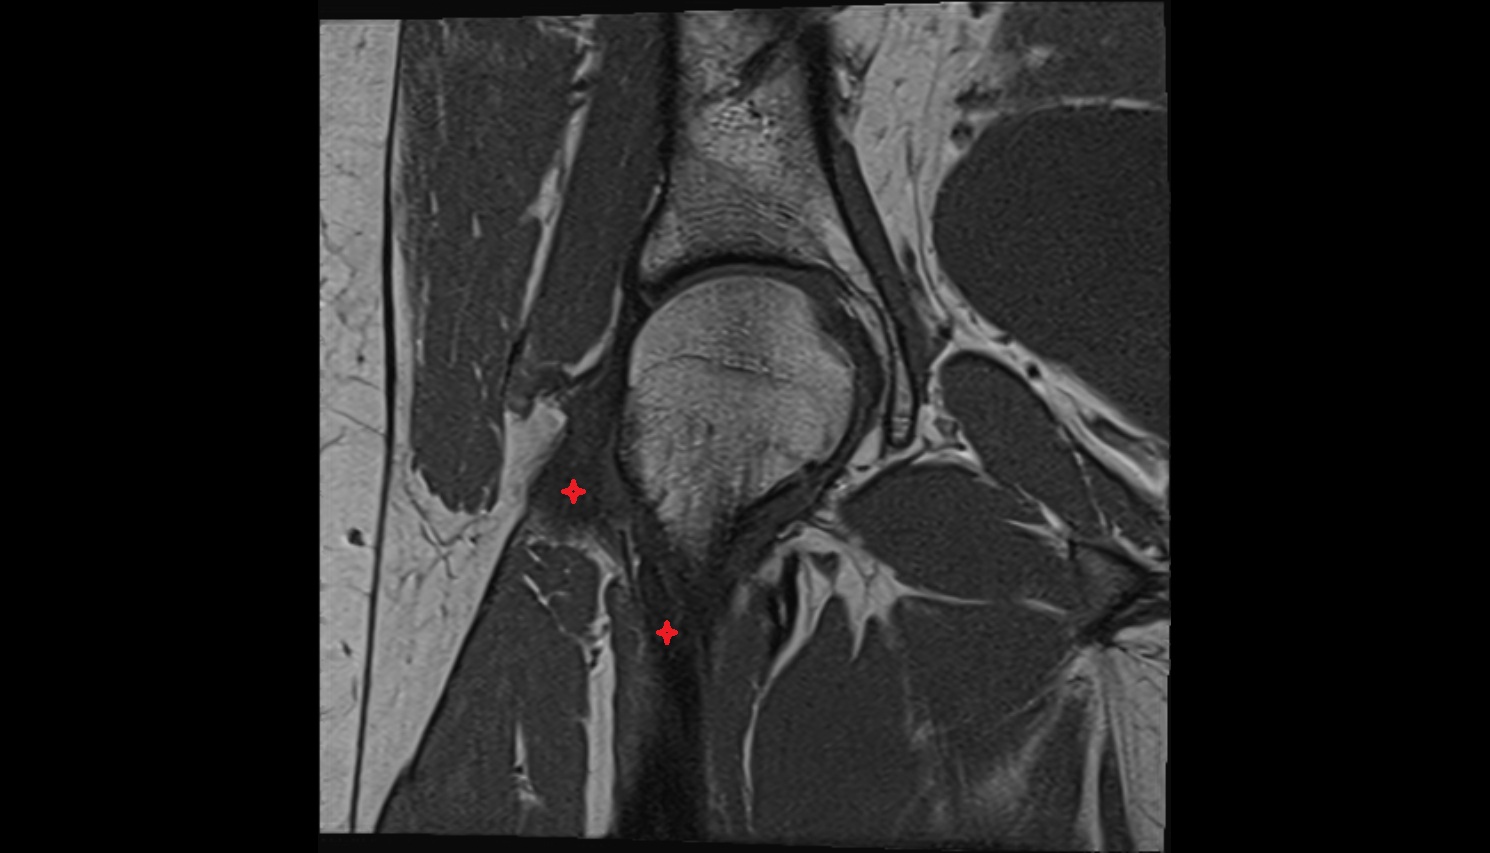

- Medial collateral ligament

- Lateral collateral ligament

- Anterior cruciate ligament

- Posterior cruciate ligament

- Medial meniscus

- Lateral meniscus

- Knee Joint